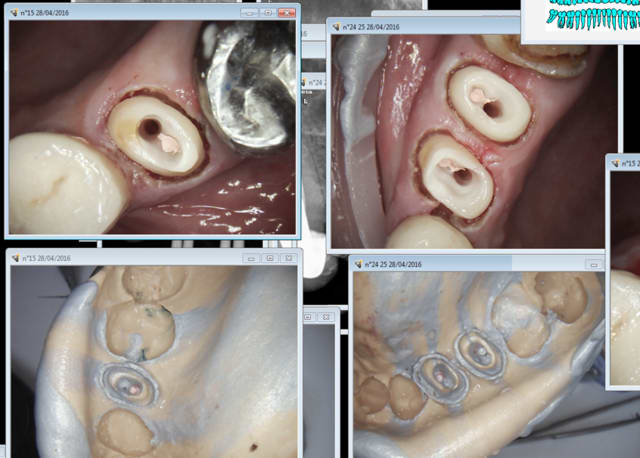

Ce que tu fais ? endo empreinte ic coiffe dans la séance.

1H 30 : pose ic coiffe 11 13 14 ( manque la 12 fait chier) endo taille empreinte 15 24 25.

Puisqu'on parle de cette 15 convenons qu'un onlay avec un recouvrement d'une cuspide lui aurait peut-être été plus profitable. Onlay invendable vs le combo IC/CCM sans reste à charge. On est bien d'accord.